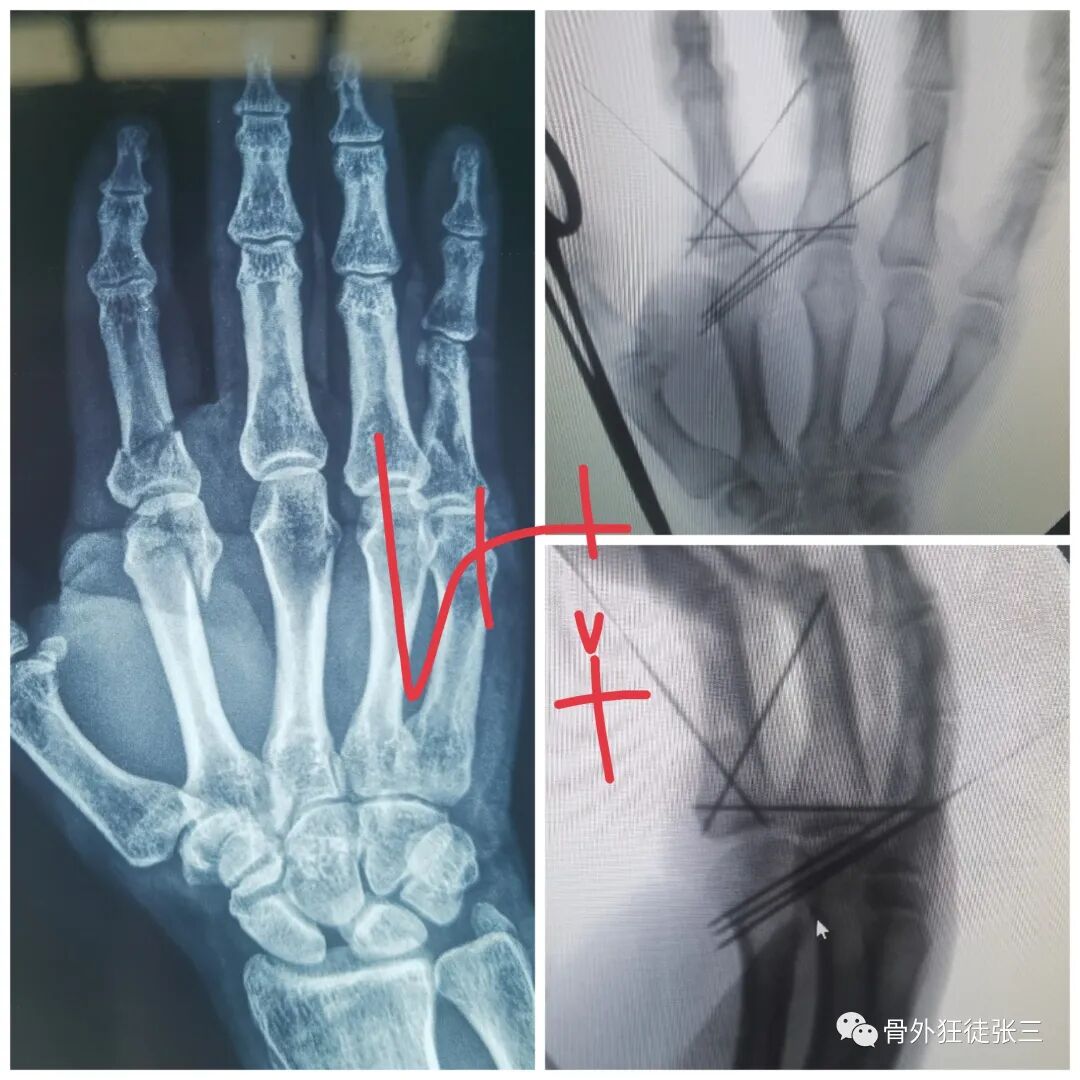

病例1,第5掌骨基底骨折,闭合复位克氏针支架,无需石膏,门诊手术,术后即刻恢复正常工作。

病例2,第4掌骨螺旋型骨折,经皮撬拔,克氏针支架。

病例5,开放性第3、4掌骨骨折,隔山打牛,克氏针支架。

病例6,开放性第2345掌骨骨折,克氏针支架

病例7,开放性掌骨,指骨骨折,克氏针内固定

病例9,第4掌骨螺旋骨折,指骨骨折,闭合复位,克氏针支架。

病例13,拳击手骨折,克氏针支架,无需石膏,不影响工作。

病例18,第一掌骨基底部骨折,闭合复位,克氏针支架

病例19,第一掌骨基底部骨折,离合复位,克氏针支架

病例20,陈旧性第5掌骨头骨折,畸形,闭合复位,克氏针支架

病例21,指骨粉碎性骨折,闭合复位克氏针

病例22,陈旧性第5掌骨骨折,畸形,闭合复位克氏针支架

病例23,严重复杂手外伤,多发骨折,克氏针固定

病例32,第345掌骨开放性骨折,克氏针髓内+克氏针支架

病例34,掌骨、指骨粉碎性骨折,闭合复位克氏针